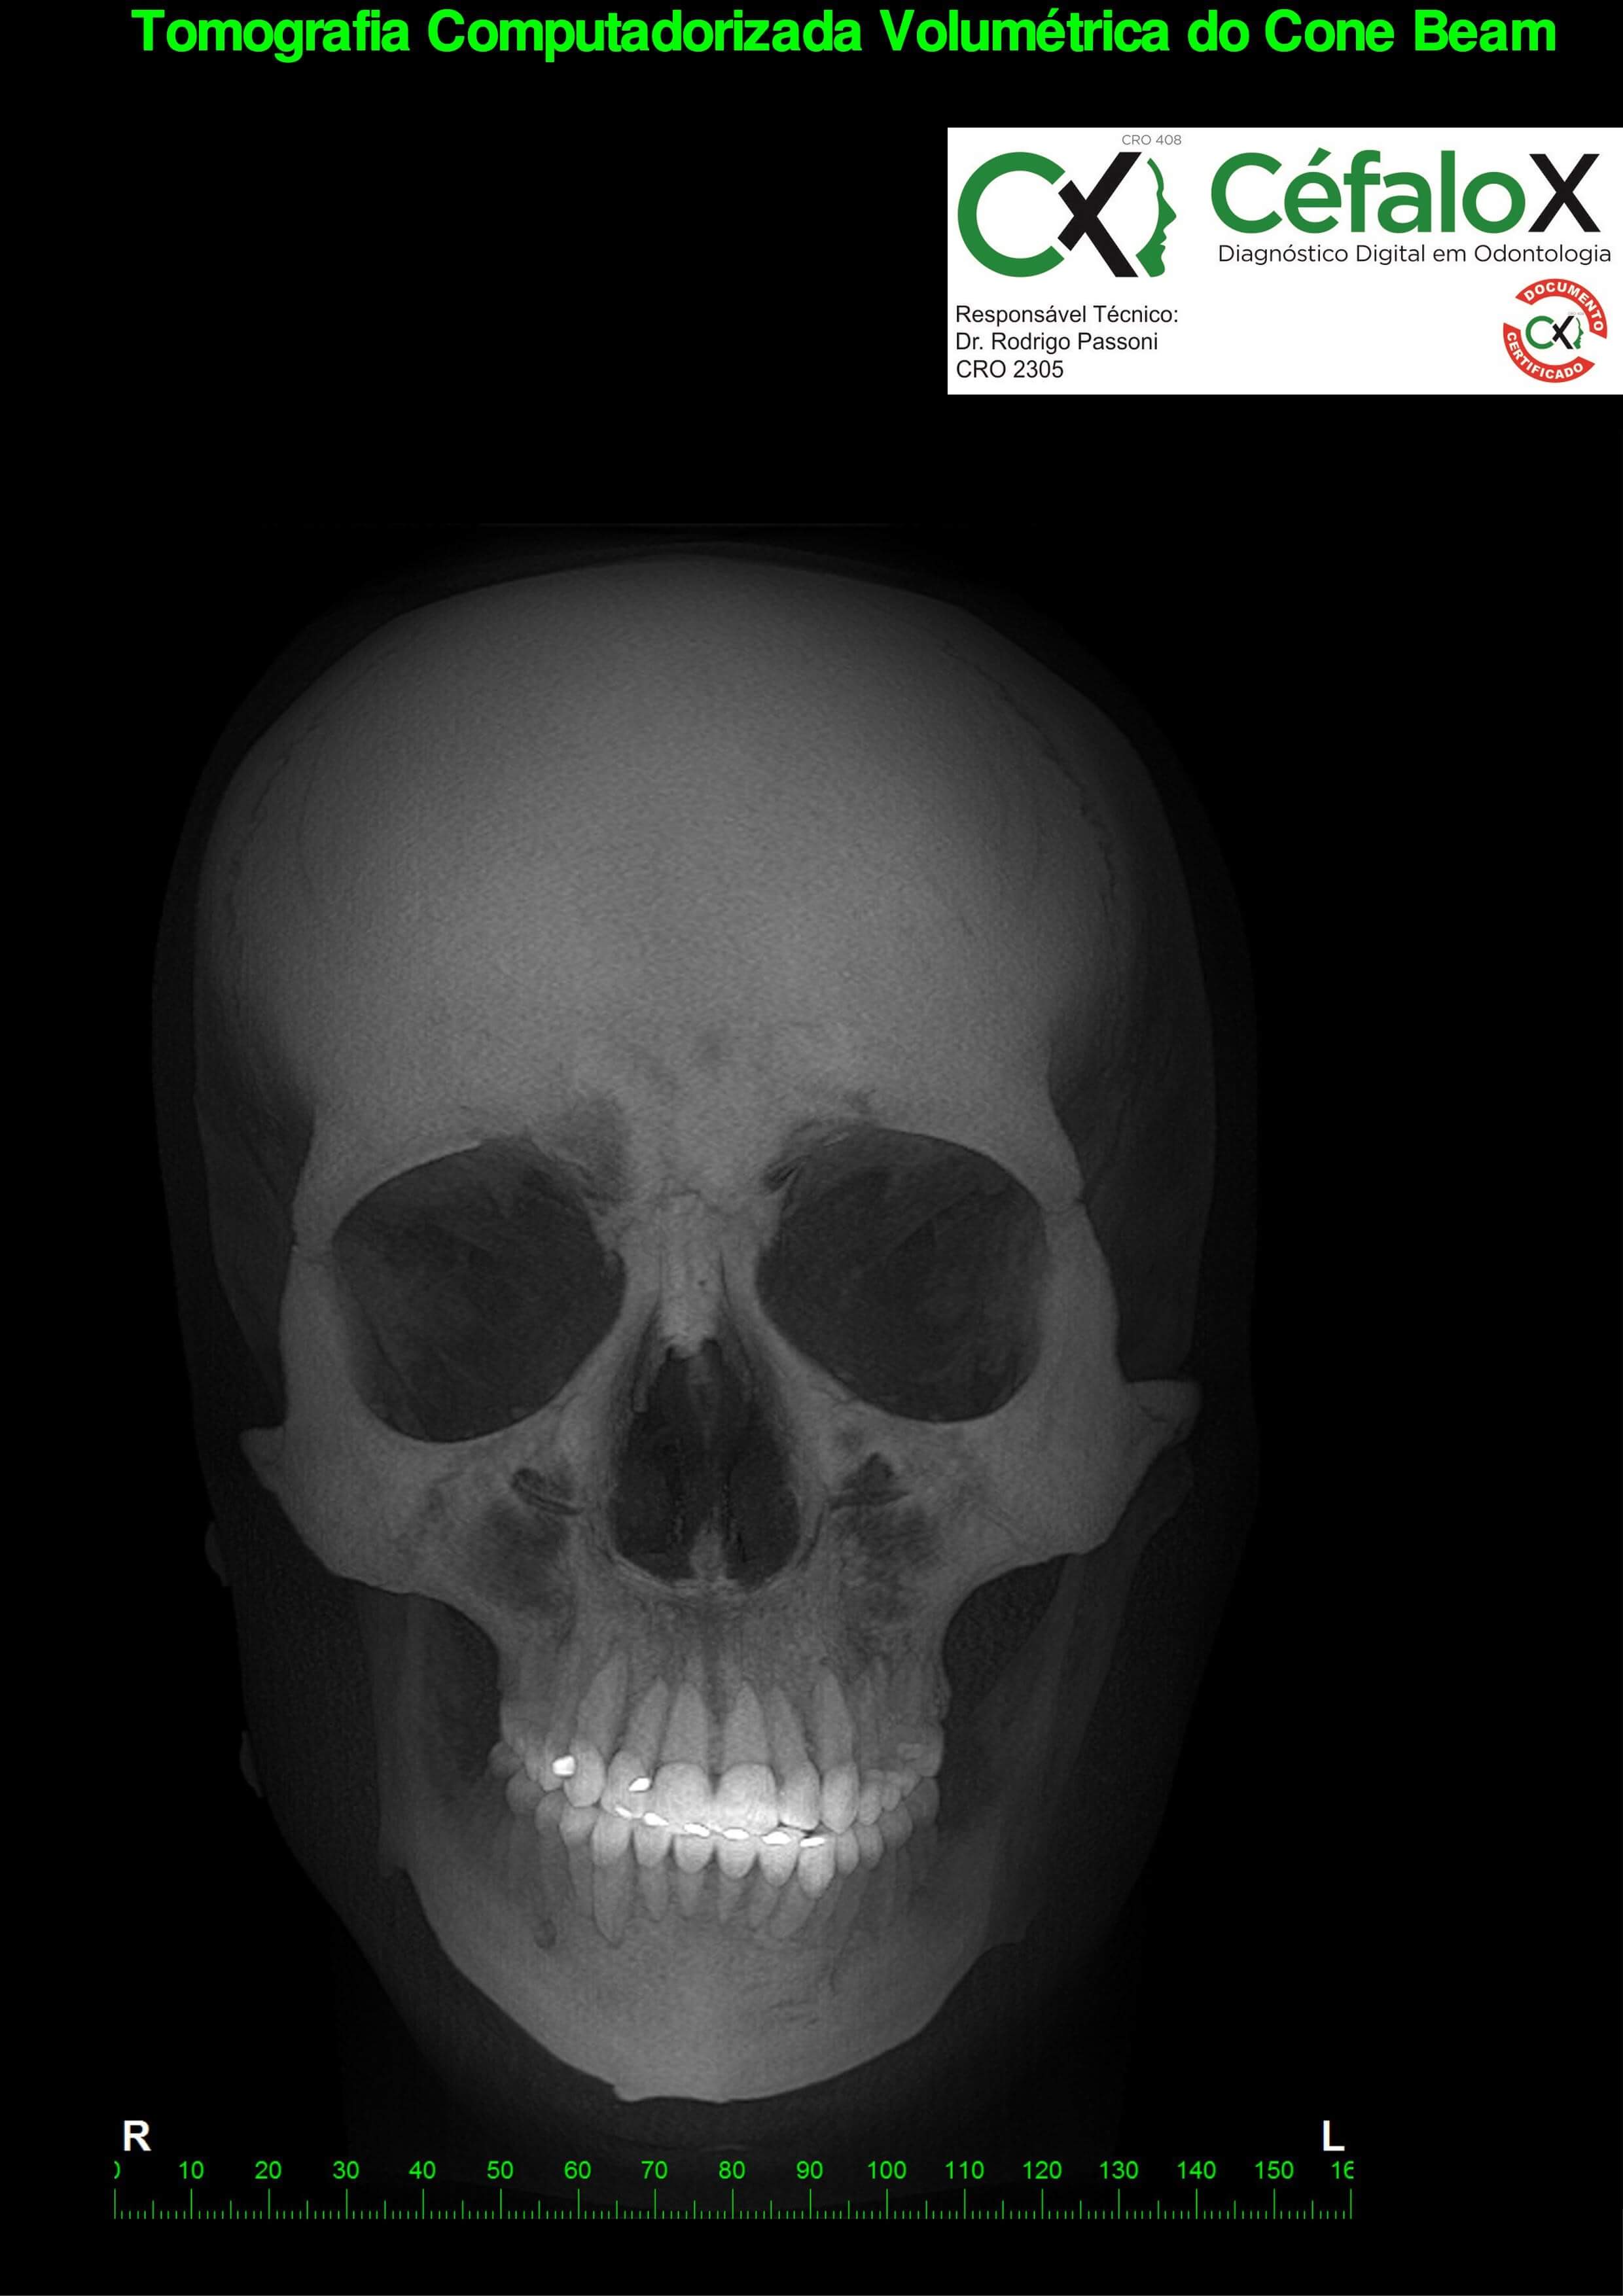

TC de face (do Hióide à Glabela), reconstrução 3D do tecido ósseo, radiografia panorâmica, telerradiografia lateral com traçado, cortes transversais e axial de maxila e mandíbula e arquivo DICOM- entregue em pasta de Pvc.

TC de face (do Hióide à Glabela), reconstrução 3D do tecido ósseo, radiografia panorâmica, telerradiografia lateral e frontal com traçado, cortes transversais e axial de maxila/mandíbula e arquivo DICOM – entregue em pasta de Pvc.

TC de face (do Hióide à Glabela), reconstruções 3D do tecido mole/ósseo/vias aéreas, radiografia panorâmica, telerradiografia lateral e frontal com traçado, cortes transversais e axial de maxila/mandíbula, ATM e arquivo DICOM – entregue em pasta e caixa de Pvc.